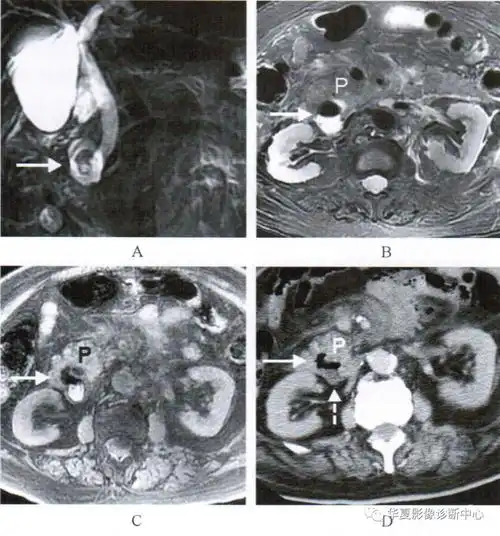

温故知新十二指肠憩室的影像诊断